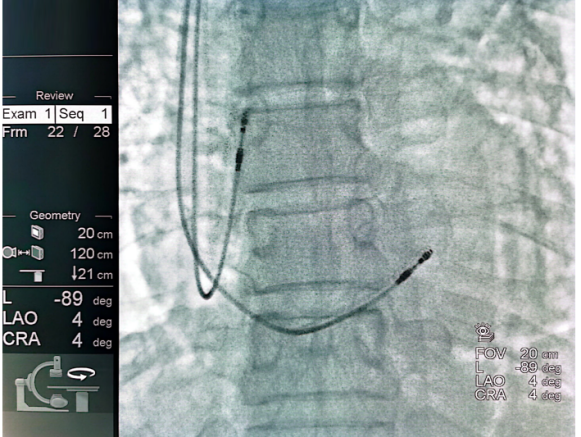

同时患者伴有脊柱疾病、脑梗等病史,充分考虑患者未来明确有3.0T场强MRI检查需求。因此,为患者选择植入雅培3.0T核磁兼容双腔起搏器PM2282。手术分别将右房、右室起搏导线分别植入于右心耳及右室间隔部,术中参数测试良好。

术中最终留影图